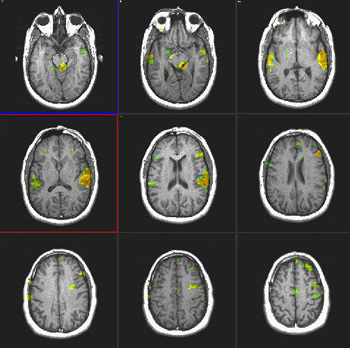

Studies in Late Bilinguals

| Subject | Right handed 34 year-old-woman. Native language: Spanish | ||||||

| Paradigm | Type: Verbal fluency task ON: Retrieve verbs related to presented nouns OFF Spell given words | ||||||

| Statistics |

| Activation | There is activation of Broca's area in both languages. The right thalamic activation is noted only in the second language. There is also greater activation of the right inferior frontal gyrus in the second language than in the mother language. SMA is more pronounced on the right in both languages. |